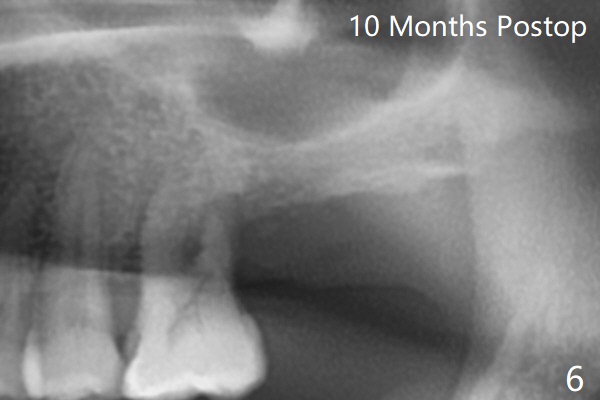

A 54-year-old man returns to clinic 5 months post SRP with chief complaint of UL loose tooth (#15, Fig.1). Since the remaining bone is limited after extraction, it is apparently unsuitable for immediate implant (Fig.2). Socket preservation seems to be able to gain bone height near gingival margin (Fig.3 red line). In fact 1 cc of cortical and cancellous bone mixture is used; after heavy debridement the bone graft is deposited on the distal root surface of the tooth #14 (Fig.4 arrow). The bone increases not only coronally, but also apically (Fig.5 blue lines, as compared to red lines denoting the original bone height). The bone reduces in height 10 months postop (Fig.6). Sinus lift is required for placement of a short implant (Fig.7). Socket preservation does not prevent post-extraction bone loss.